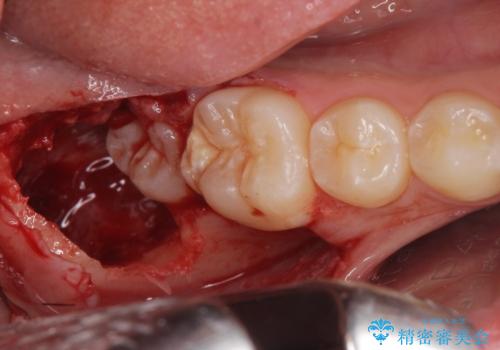

無事抜歯を行うことができました。

1週間後に傷口チェックと抜糸を行う必要があります。